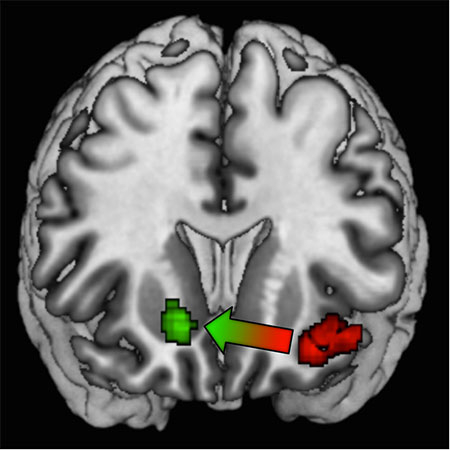

Grâce à l’imagerie par résonance magnétique cérébrale, l’équipe de recherche a aussi pu valider cet algorithme d’un point de vue neurobiologique, en montrant qu’il explique les variations d’activité cérébrale dans le cortex préfrontal médian, une zone du cerveau connue pour être impliquée dans la prise de décision. L’IRM a également permis de trancher un débat important dans la littérature : y a-t-il des systèmes ou réseaux distincts dans le cerveau pour l'apprentissage basé sur la récompense et celui basé sur la punition ? Des données expérimentales contradictoires existent, certaines suggérant que oui, d'autres que non. L’analyse démontre qu’au départ, lorsque les sujets ne semblent pas encore avoir bien appris la valeur du contexte, le système d'apprentissage basé sur la récompense (le striatum ventral) et celui basé sur la punition (l'insula) sont tous les deux activés. Puis, à mesure que la contextualisation des valeurs négatives se met en place, l’insula s'active de moins en moins, et les essais d'apprentissage dans le contexte de punition se mettent à impliquer le striatum ventral qui s'active de plus en plus.

La figure montre des activations cérébrales dans deux régions, le striatum ventral (en vert) et l’insula antérieur (en rouge), qui sont connues pour travailler en opposition et être impliquées dans l’apprentissage par récompense et celui par punition, respectivement. Dans notre étude nous montrons que la contextualisation des valeurs supprime la nécessité d’activer l’insula, lors de l’apprentissage par punition, produisant un transfert d’activation du système de punition vers le système de récompense à mesure que les actions acquièrent une valeur relative positive.